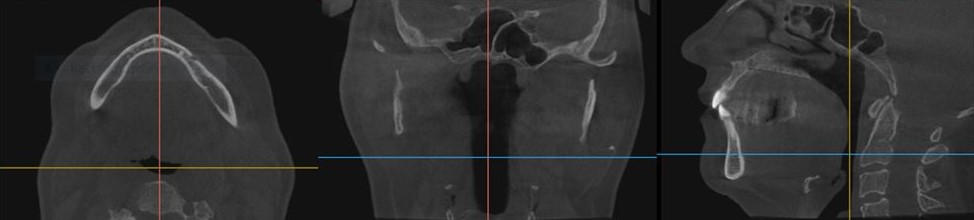

Initial cone beam computed tomography (CBCT) revealed low tongue posture (Figure 1). Figures 2, 3, and 4 show the frontal, maxillary occlusal, and mandibular occlusal views of the dentition, respectively. Clinical examination identified a scalloped tongue with low muscle tone and difficulty achieving palatal suction. Dental findings included upper and lower arch crowding, advanced tooth wear consistent with attrition, a deep skeletal bite evident on cephalometric analysis, and a marked loss of vertical dimension of occlusion (VDO) (Figures 5 and 6).

Home sleep apnea testing reported an AHI of 41.7 events/hour, with a supine AHI of 51.9 events/hour, an oxygen saturation nadir of 81%, and a respiratory disturbance index of 42.1. Radiologic interpretation of the CBCT confirmed a deviated nasal septum, severe oropharyngeal narrowing at the level of the soft palate and posterior third of the tongue, and lingual tonsillar hypertrophy. Cervical spine imaging also demonstrated intervertebral foraminal stenosis at levels C3–C5 and joint space narrowing—findings consistent with chronic forward head posture and its biomechanical consequences.32-35

Figure 1.

(more ...)